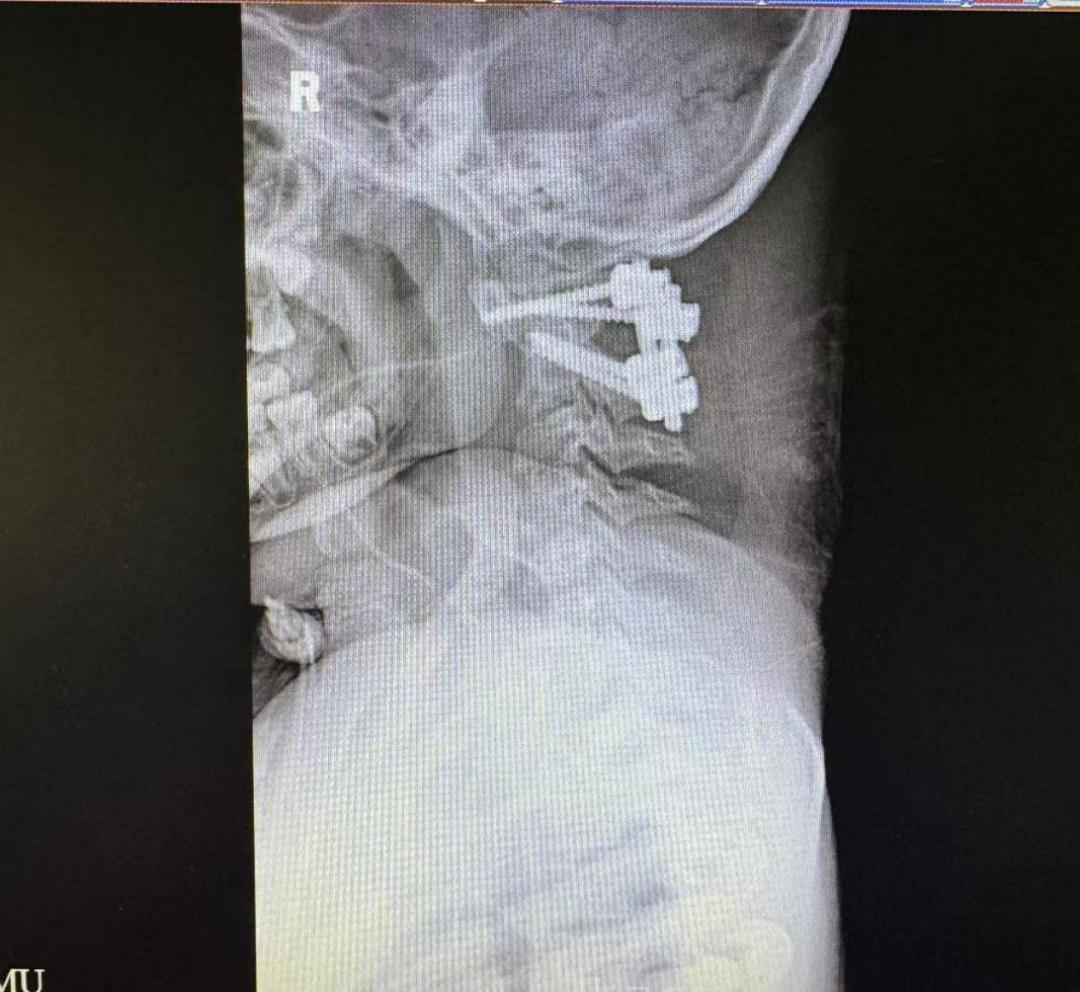

术前术后颈椎X光片

为解决这个问题,脊柱外科一科主任王亮在术前采用3D打印技术复刻了乐乐的寰枢椎模型,反复进行充分的手术模拟。几次模拟下来,王亮有了信心,决定直接实施颈椎后路手术复位手术。术中,团队紧密配合,将手术精度控制在“毫米级”,一次性精准置钉,完成寰枢椎复位与固定。

术后,医护团队为乐乐量身定制了康复方案:从最初的床上翻身训练,到辅助站立,再到步态练习和日常生活能力恢复,每一次进步都凝聚着医护人员的专业与爱心。术后一周,原先只能躺在平车上的孩子,终于带着自信的笑容,一步、两步,慢慢走向等候在病房门口的“家人”们。